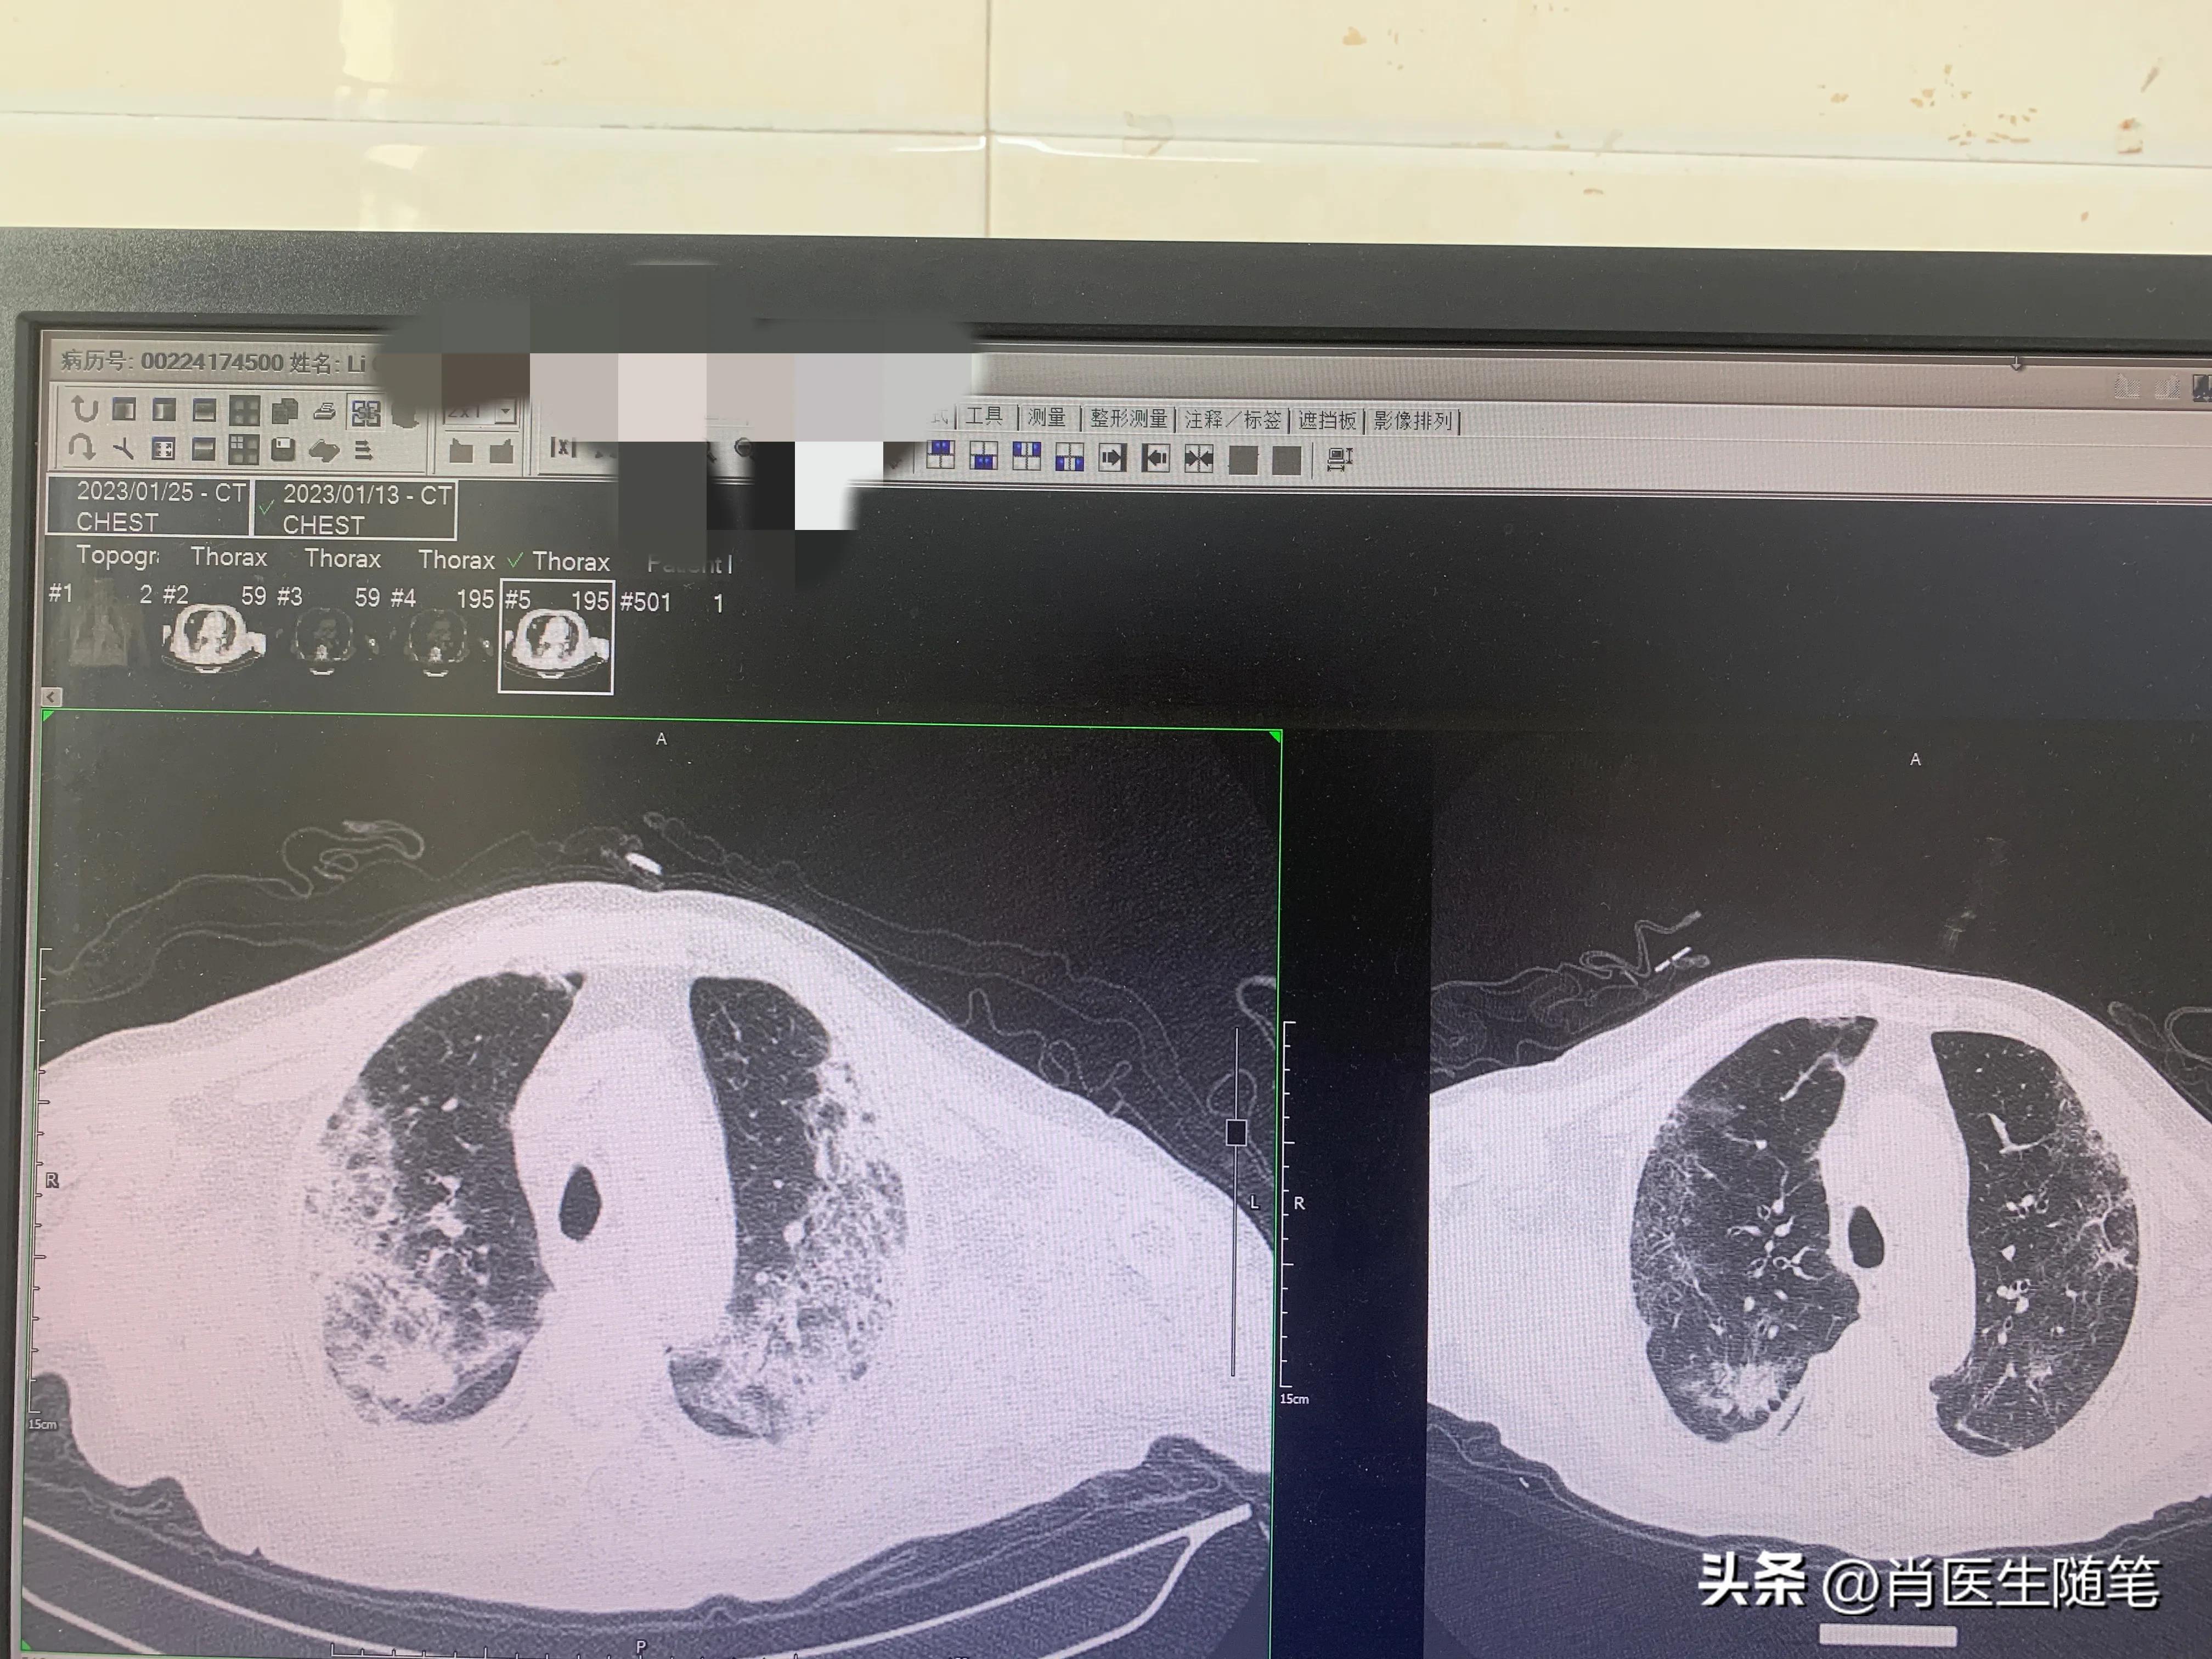

治疗后(2023-01-25)复查胸部CT,炎症较前吸收,下图是同样切面对比图。左边是13号的,右边是25号的。